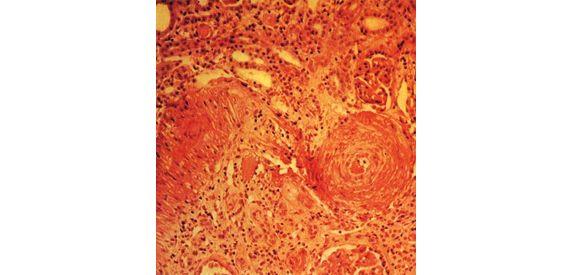

Nefroangiosclerosi Benigna NEFROANGIOSCLEROSI BENIGNA Il rene è l